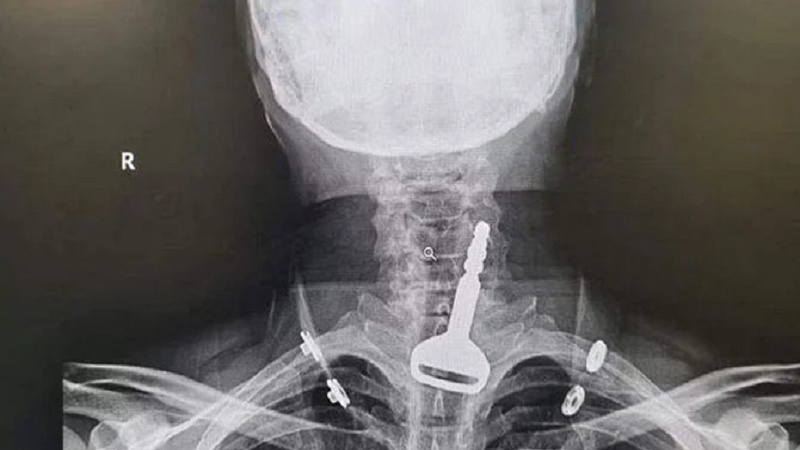

زمونږ خبریال راپور راکړی د سعودي عربستان یوه ښاریز د لوبې په وخت ناڅاپه د خپل ګاډي کلید یعني چابۍ تیرې کړې او دغه چابۍ د نوموړي سړيد غاړې د سااخیستلو په لاره کښې ښخې شوې چې له کبله یې د هغه د مړینې خطر ډیر زیات و.

د لیپارواسوپیک جراحۍ او سرجرۍ په وسیله د عربستان د دغه ښاریز د مرې د سا له اخیستلو لارې دغه چابۍ وویستل شوې.

ویل کیږي چې د عربستان ډاکټرانو د اینډواسکوپۍ په وسیله د دغه ښاریز د سا اخیستلو له نالۍ څخه د چابیو د ایستلو فیصله کړي وه خو کله چې معلومه شوه چې د عربستان دغه ښاریز د زړه مریض دی او دغه اینډواسکوپي د هغه لپاره خطرناکه کیدلای شي نو ډاکټرانو د لیپارواسکوپیک جراحۍ په وسیله اپریش وکړ او دغه جراحۍ بریالۍ شوه او د سړي د سا د اخیستلو له نالۍ څخه د چابیو په ایستل کیدا سره د هغه ژوند بچ شو.